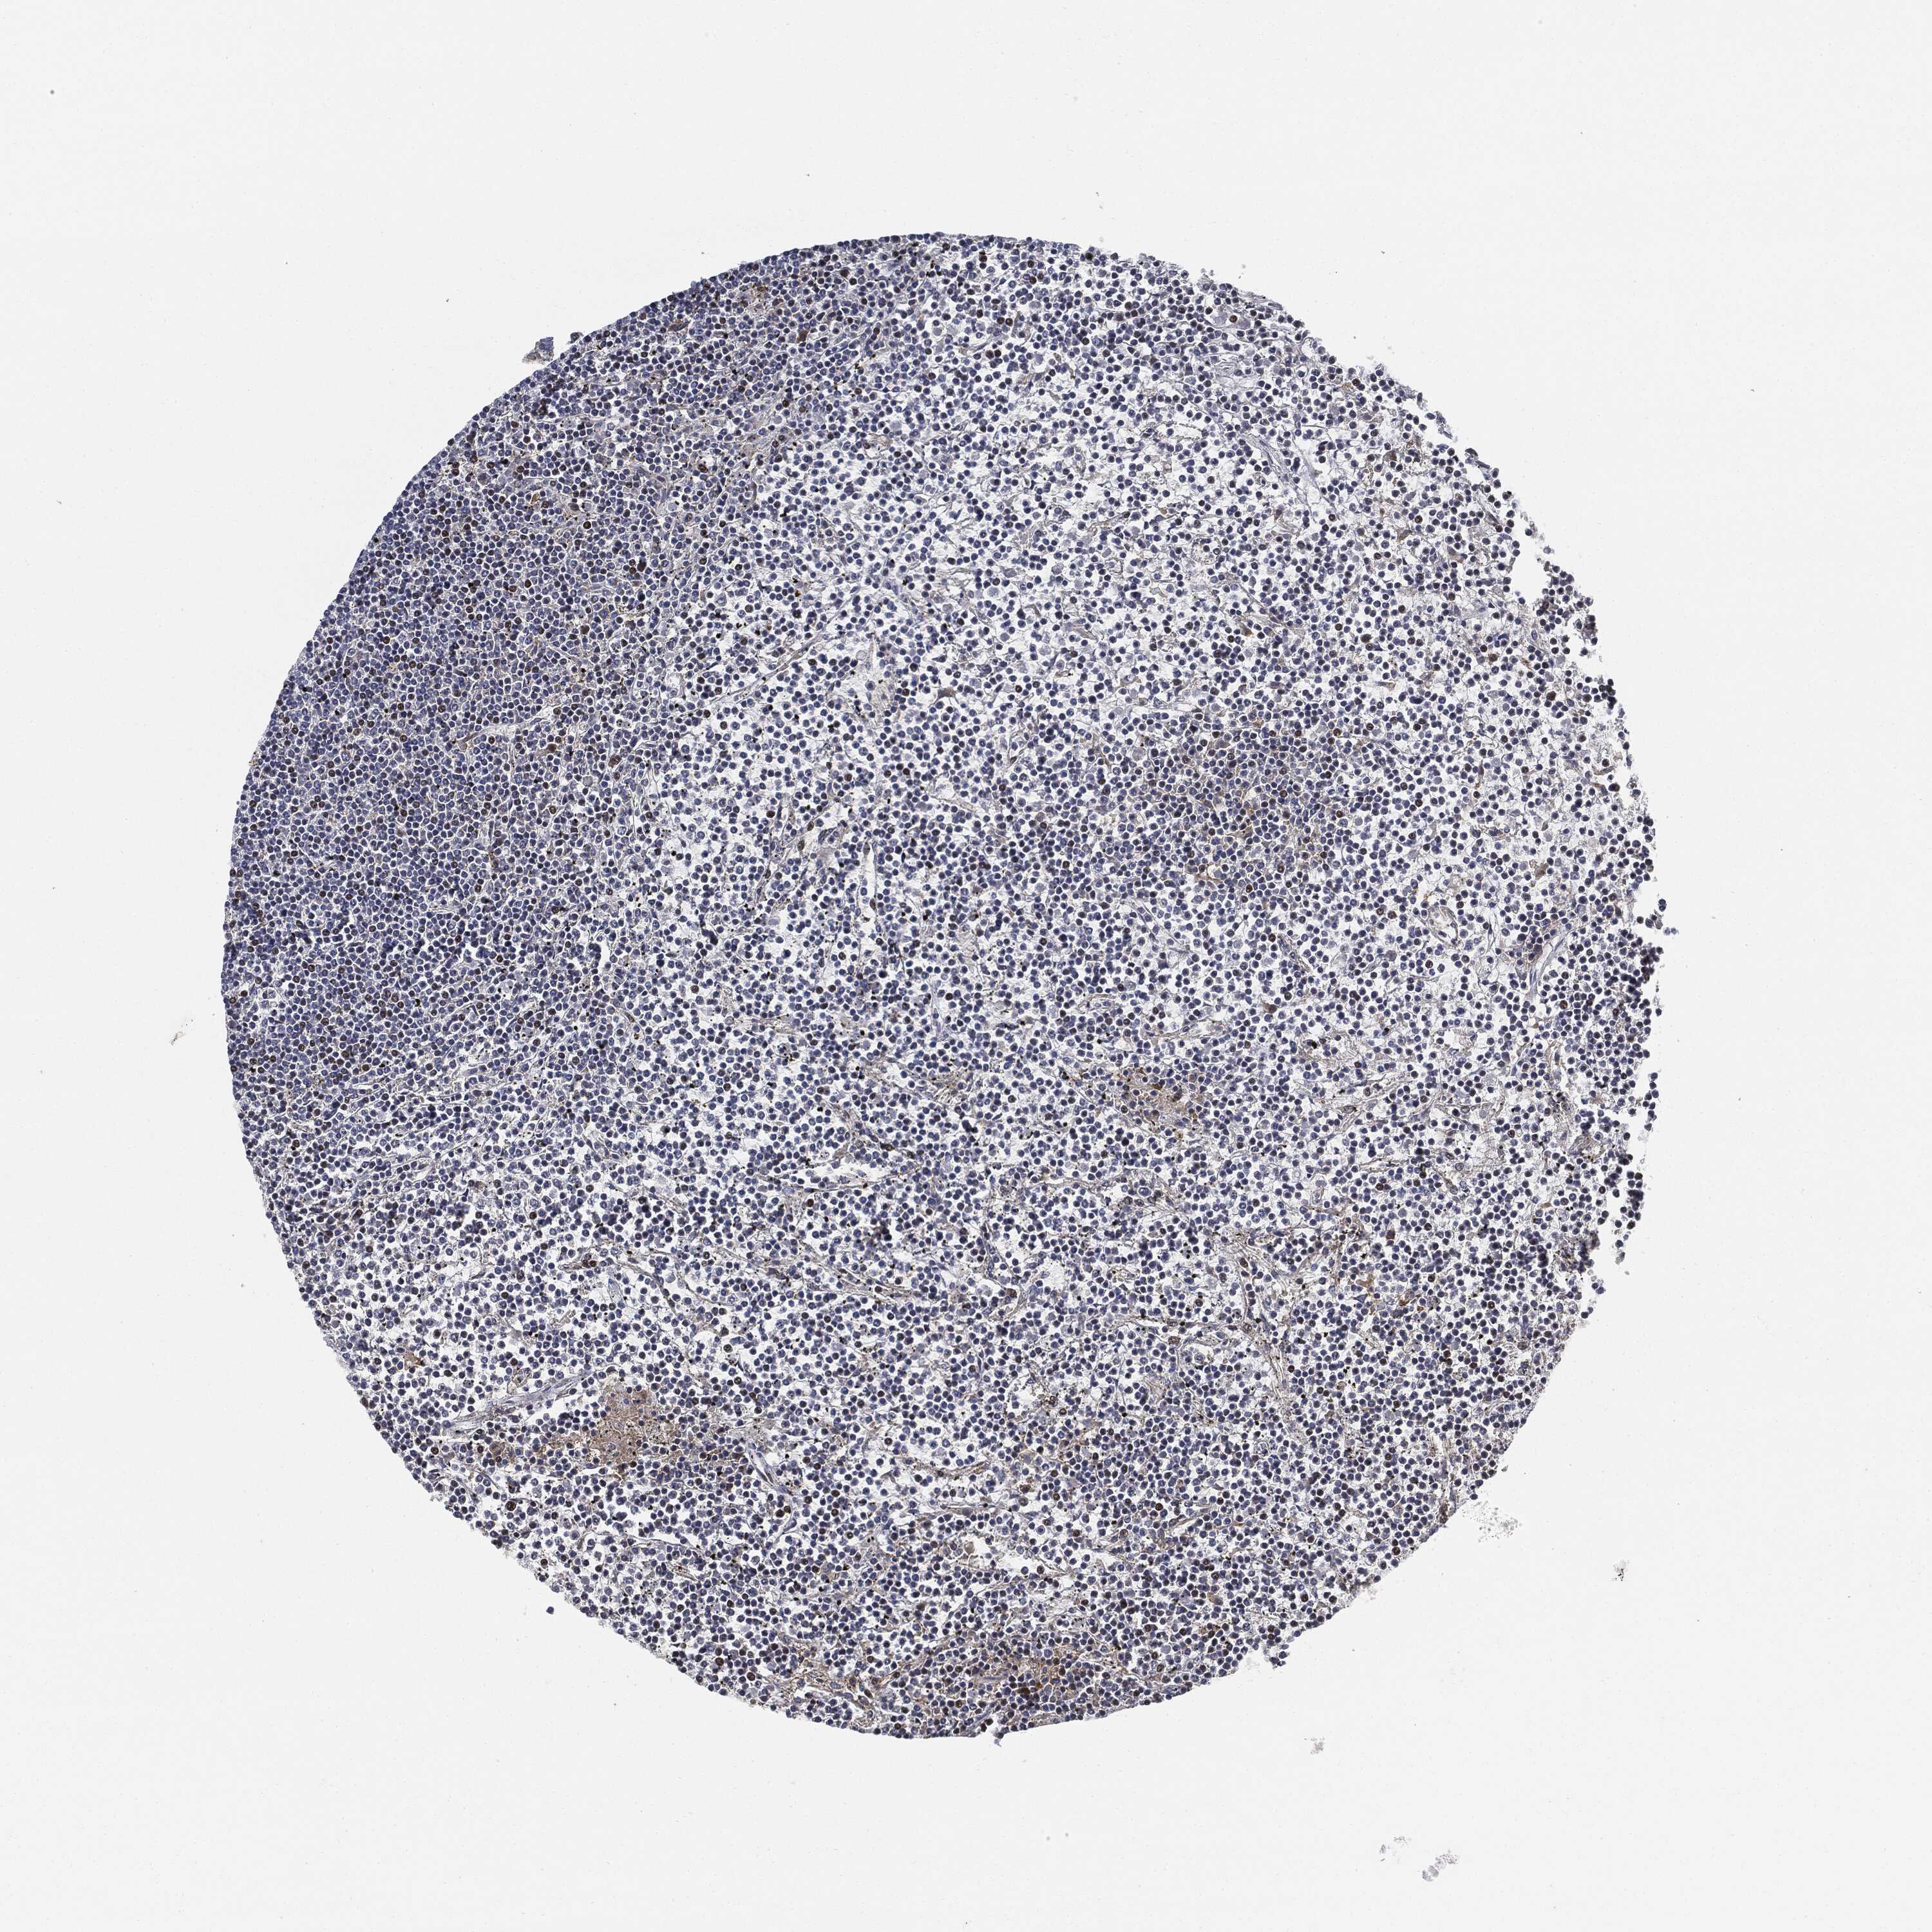

LYMPHOMA - Protein expressioni

A mouse-over function shows sample information and annotation data. Click on an image to view it in a full screen mode. Samples can be filtered based on level of antibody staining by selecting one or several of the following categories: high, medium, low and not detected. The assay and annotation is described here.

Antibody stainingi

Antibody staining in the annotated cell types in the current human tissue is reported as not detected, low, medium, or high, based on conventional immunohistochemistry profiling in selected tissues. This score is based on the combination of the staining intensity and fraction of stained cells.

Each image is clickable and will lead to virtual microscopy that enables deeper exploration of all samples and also displays staining intensity scores, fraction scores and subcellular localization as well as patient and tissue information for each sample.

Antibody CAB076385

Staining

Not detected

Negative

None

Malignant lymphoma, non-Hodgkin's type, Low grade